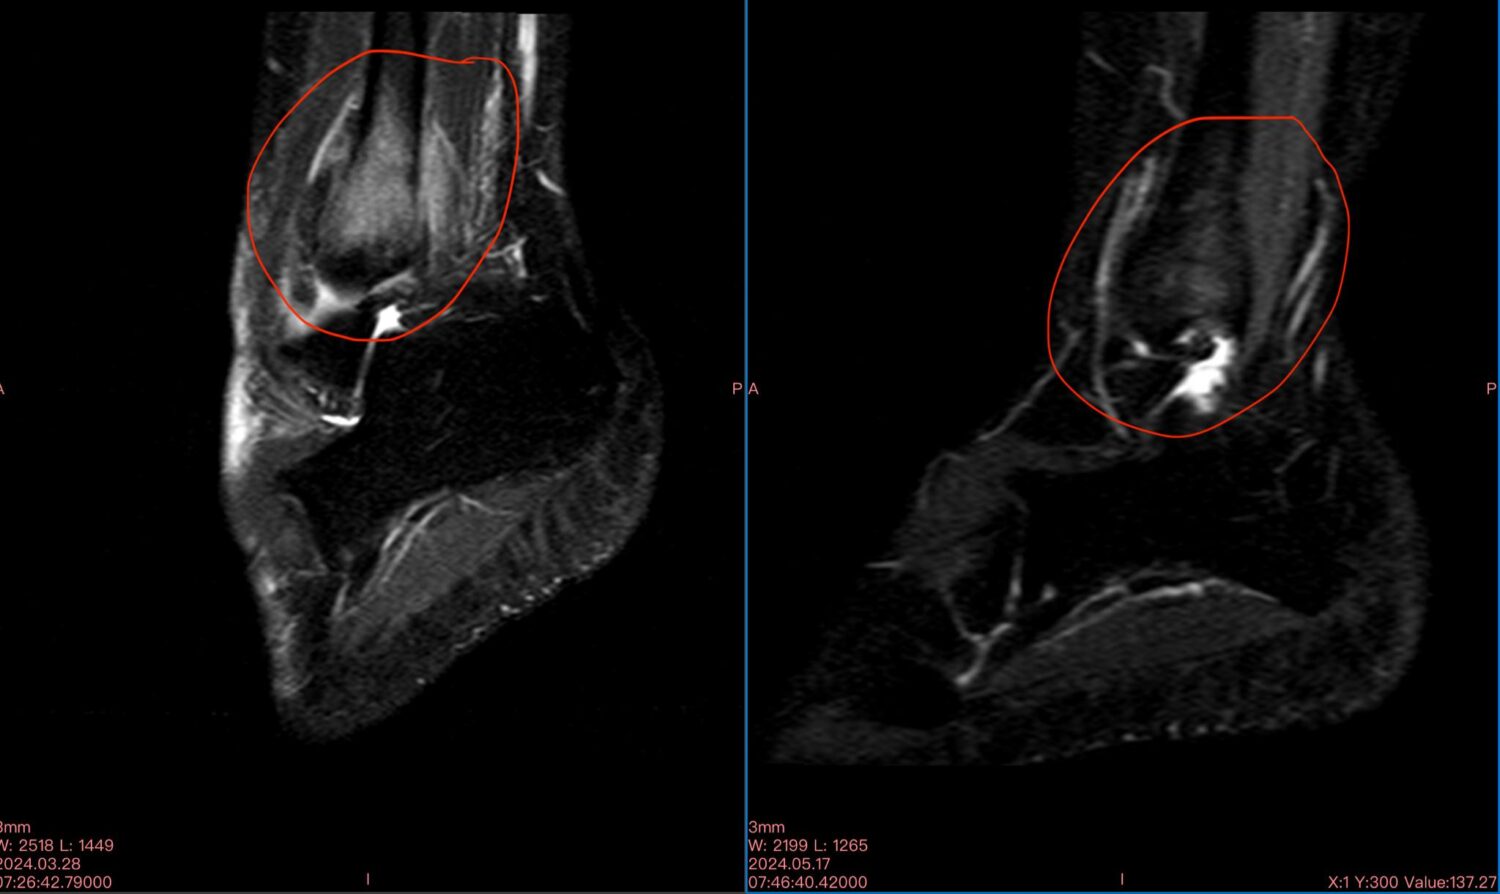

Μαγνητικές ασθενών με οστικό οίδημα πριν (αριστερή φωτογραφία) και μετά (δεξιά φωτογραφία) την θεραπεία με διαμαγνητική αντλία: